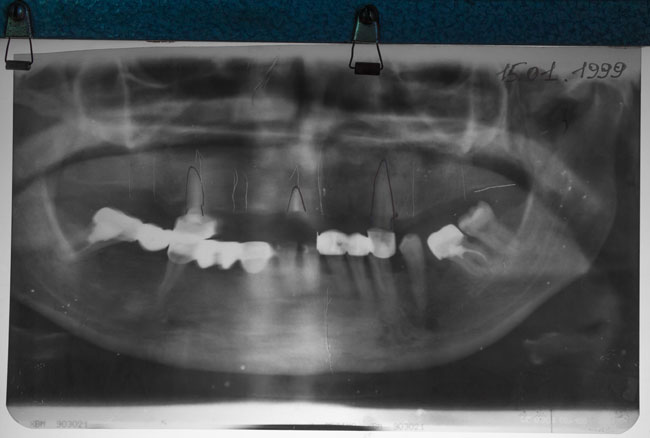

Patient P., 49 years old is being treated at KM “Bobruisk City Dental Clinic No 1” in 1998.

More than 15 years ago, on 22.02.1999, dental implants were placed in maxilla region 1.5; 1.3; 1.1; 2.4 – 2.6. A cylindrical implant was united with a plate implant (see Fig. 1, 2).